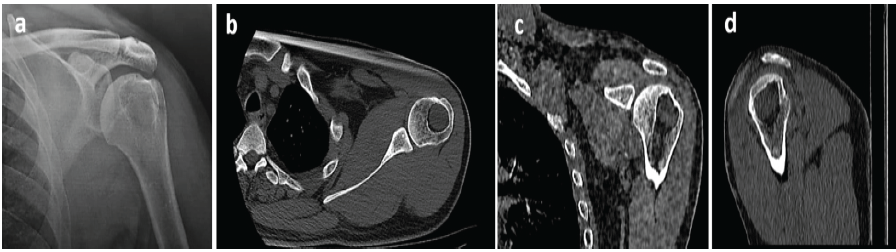

A 36-year-old male presented with a 6-month history of progressive left shoulder pain, which was exacerbated by activities and relieved only partially with medications. Plain radiographs of the left humerus showed an eccentrically-located lytic lesion within the proximal humeral metaphysis, in proximity to the greater tuberosity (Fig. 1). Computed tomography revealed a well-defined, peripherally enhancing cystic lesion with a homogenous soft tissue density matrix (Fig. 1).

Figure 1: (a) Pre-operative radiograph demonstrating a lytic lesion in the proximal humerus, (b) axial, (c) coronal, and (d) sagittal computed tomography sections showing the lesion at its maximum diameter in each anatomical plane.